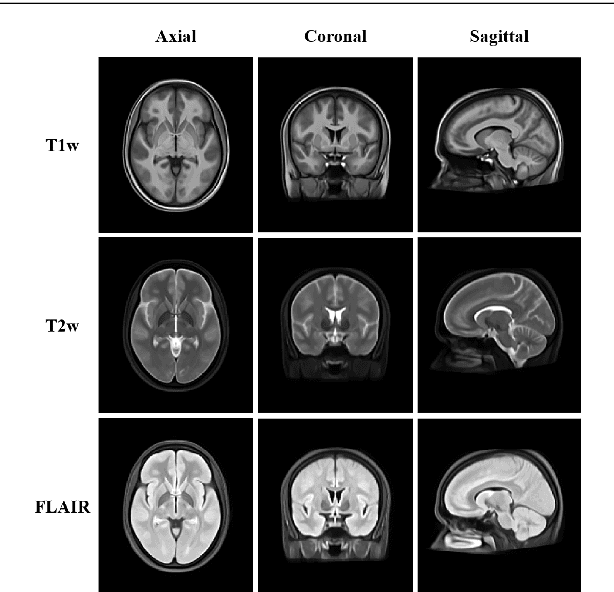

Abstract:Introduction: Multiple Sclerosis (MS) is a chronic disease that affects millions of people across the globe. MS can critically affect different organs of the central nervous system such as the eyes, the spinal cord, and the brain. Background: To help physicians in diagnosing MS lesions, computer-aided methods are widely used. In this regard, a considerable research has been carried out in the area of automatic detection and segmentation of MS lesions in magnetic resonance images (MRIs). Methodology: In this study, we review the different approaches that have been used in computer-aided detection and segmentation of MS lesions. Our review resulted in categorizing MS lesion segmentation approaches into six broad categories: data-driven, statistical, supervised machine learning, unsupervised machine learning, fuzzy, and deep learning-based techniques. We critically analyze the different techniques under these approaches and highlight their strengths and weaknesses. Results: From the study, we observe that a considerable amount of work, around 25% of related literature, is focused on statistical-based MS lesion segmentation techniques, followed by 21.15% for data-driven based methods, 19.23% for deep learning and 15.38% for supervised methods. Implication: The study points out the challenges/gaps to be addressed in future research. The study shows the work which has been done in last one decade in detection and segmentation of MS lesions. The results show that, in recent years, deep learning methods are outperforming all the others methods.